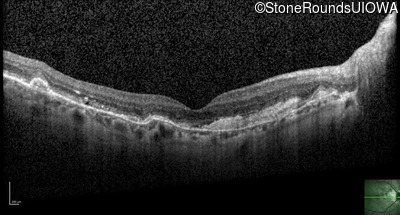

Optical Coherence Tomography - Left - 20/20 -2

Exemplar / OCT Stack

OCT Stack